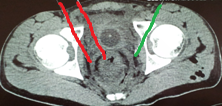

Κόκκινα βέλη. Παχυσμένο τοίχωμα ορθού. Πράσινο βέλος. Περιτονία του μυός ανελκτήρα του πρωκτού (Ευγενική παραχώρηση Dr. V. Penopoulos)